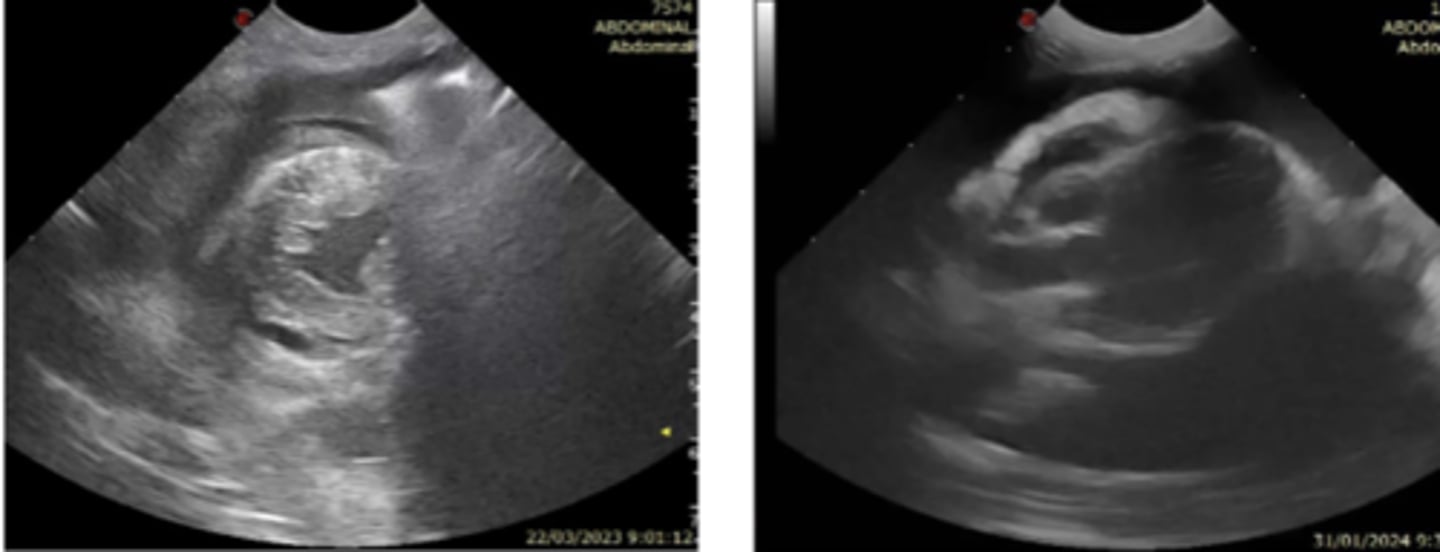

dilatación-torsión gástrica

patología: